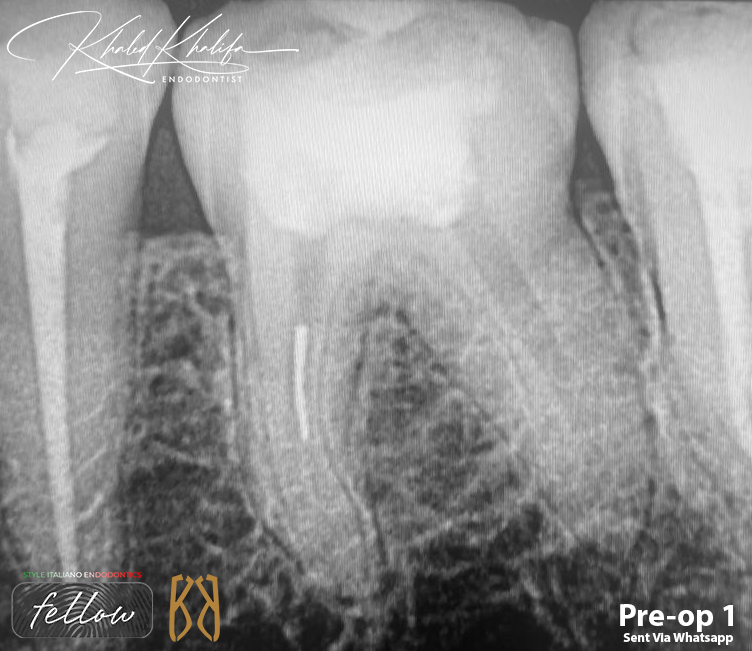

Unfortunately, in this case as you can see, the previous doctor tried to retrieve/bypass the file before referring the case as seen in the first 2 photos they made a perforation above the broken file in inner wall.

Broken File Retrieval + Managment of Acute Curve + Sealing Perforation and Coronal part of the root with Bioceramic Material.